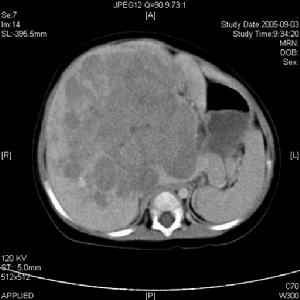

實體腫瘤的腎損害B超圖(3)單純系膜增生性病變;